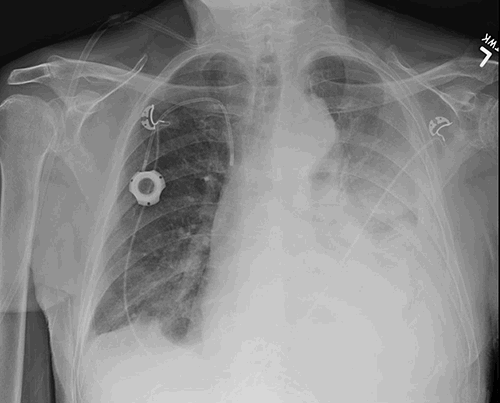

Figure 3. 3-dimensional reconstruction of CTA in coronal and oblique views demonstrating the catheter within the TAAA

Upon placement, there was immediate brisk and bright red blood return from the catheter as well as transient hypotension that responded to a saline bolus. The catheter was clamped, and a post-procedure non-contrasted CT of the chest confirmed catheter placement within the aneurysm sac of his known TAAA. The patient remained hemodynamically stable after the initial transient drop in blood pressure and was transferred emergently to our institution. A 1 mm slice CTA was obtained for better anatomical detail, three-dimensional reconstruction, and centerline measurements in the event that aortic repair would be required (Figure 2 and Figure 3). At the site of chest wall entry, the aneurysm sac was immediately adjacent to the posterior chest wall. The catheter was primarily traversing organized, mural thrombus, but the curved distal tip was just within the patent lumen.